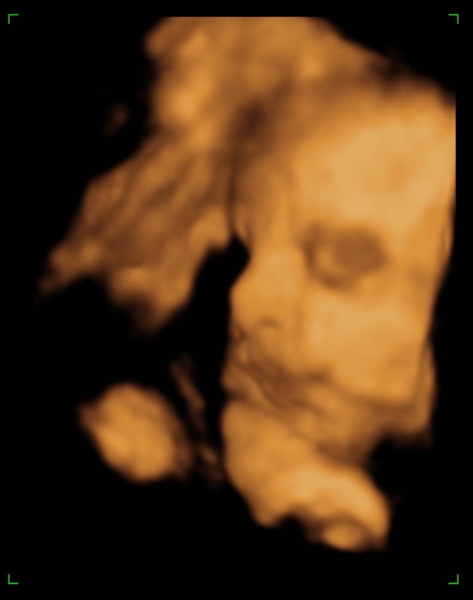

Tegnap megjártuk a 4D-t, nagyon szép husis a kisasszony :lol: persze aludt, nem kommunikált velünk, akármit ettem, ittam, csináltam. :lol: De azért féloldalasan aludt, úgyhogy csak láthattuk, volt mosoly, ásítás, fintor :lol: :lol:

Ja, és itt is megállapították, hogy nagy a talpa :lol: :lol: :lol: És a fejecskéje is, úgyhogy azt mondták majd megdolgoztat szülésnél, gondoltam "tök jó" :lol: :roll:

Méretek:

BPD - 8,17 cm

HC - 31,02 cm

AC - 28,59 cm

FL - 6,36 cm

Tappancs - 7,1 cm :lol: :lol: (s azt mondta a nő, hogy a talp általában ugyan akkora, mint az FL, tehát Dorkáé, nagy pacsker :lol: )

Becsült súly: 2078 gramm

Azt mondta, hogy ha 40 hétig bent marad, akkor 3400-3600 gramm körüli baba lesz. És tankönyv szerint halad gyarapodásban :lol: . Jaaa, és lesz haja:lol:

Ja, és a képek lemaradtak :D

Kép mosolygom:)

Kép ásítok, UFO nyitott szemeimmel:))))

Kép profilból

Kép nagy tapppppancsom:)

Kép

Persze a kis keze mindenhol ott van :lol: Bocsi, ha picit sok voltam :oops: 8)